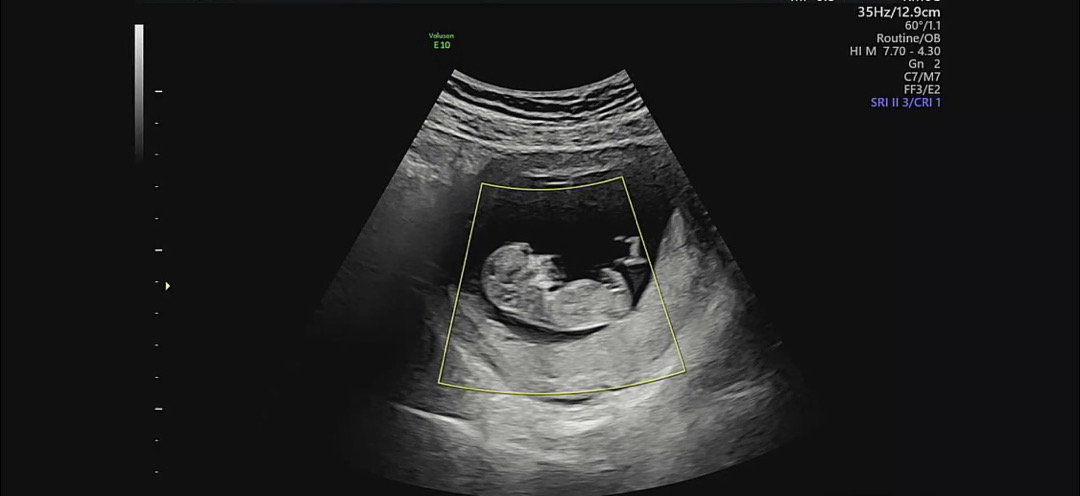

성별을 알수있을까요 ?!?